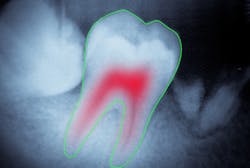

Root canals

One essential thing about root canal treatment is that it must be complete but not excessive. It is particularly important that endodontic treatment be accompanied by a detailed x-ray or CBCT examination of affected roots with the most precise measurement of root canal length and shape. But this task can pose challenges, particularly when a tooth has multiple canals and/or severely curved canals. To address this problem, dentists may call for a second-reader support of a dental image analysis system. By now, scientists have proposed many approaches to root canal identification and measurement.

Another study suggests analyzing micro-CT and CBCT slices instead. Applying computer vision algorithms to high-resolution slices creates a 3-D model of a root canal that reflects its shape with sufficient precision. The proposed method (4) is based on fuzzy c-means clustering, an unsupervised machine-learning technique used for image segmentation. The algorithm groups imaging data into clusters corresponding to the root canal and surrounding tissues. After each slice is segmented, the software creates a 3-D reconstruction of the root canal(s) with all the twists and curves. The researchers reported a success rate of 92% and concluded that the proposed technique is accurate enough to use in endodontic practice.